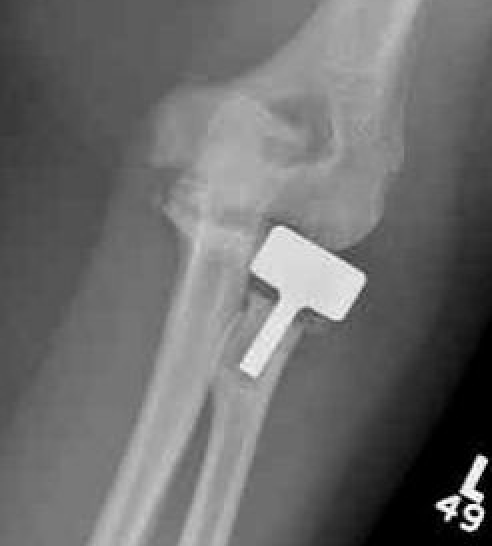

Overstuffing

| Lesser sigmoid notch | Symmetry of ulnohumeral joint |

|---|---|

|

Radial head shoulder articulate with lesser notch

Ensure no gapping of lateral ulnohumeral joint |

- cadaveric study

- increased medial ulno-humeral joint line gapping with overlengthening of 6 or 8 mm

- increased lateral ulno-humeral joint line gapping with overlengthening of 2 mm